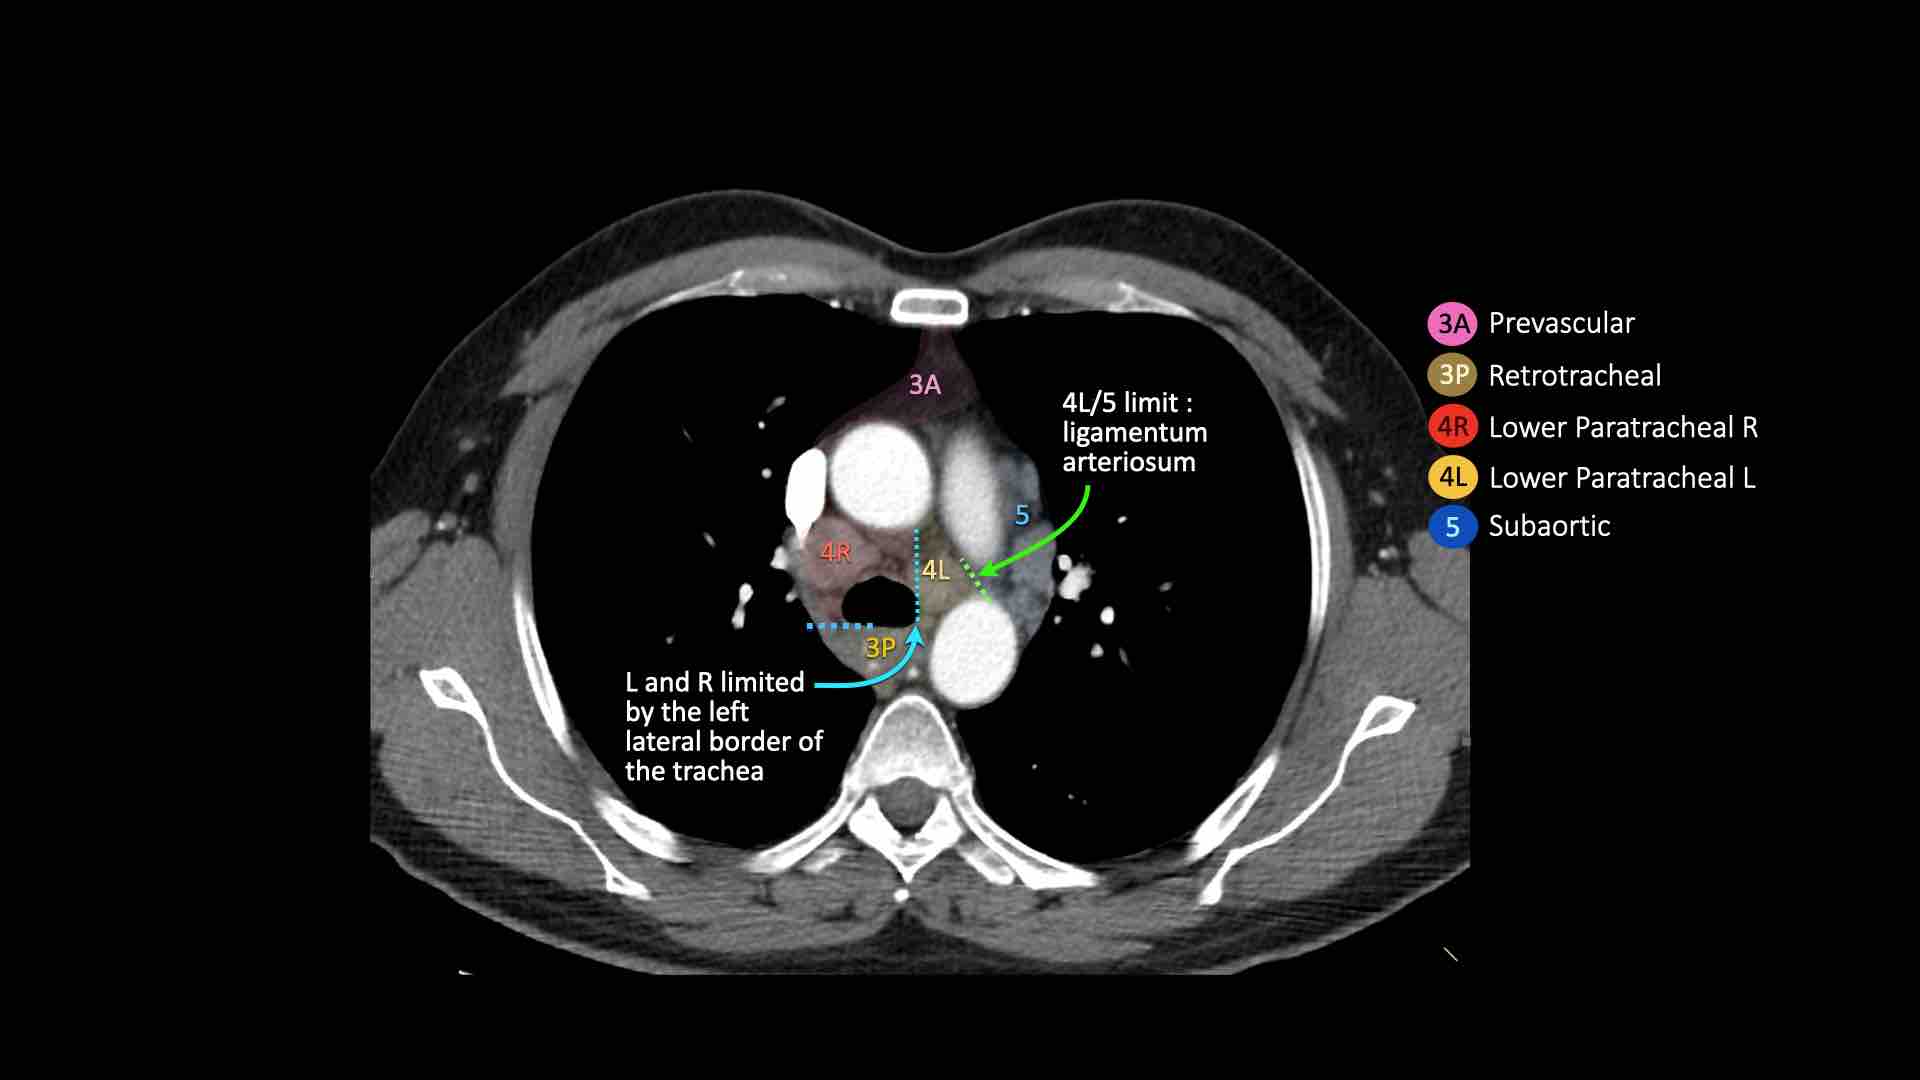

4L. Hạch cạnh khí quản dưới bên trái

Hạch nhóm 4L là các hạch cạnh khí quản dưới nằm bên trái bờ trái của khí quản, giữa đường nằm ngang tiếp tuyến với bờ trên quai động mạch chủ và đường tiếp tuyến với bờ trên động mạch phổi trái.

Nhóm này bao gồm các hạch cạnh khí quản nằm ở phía trong dây chằng động mạch.

Hạch nhóm 5 (cửa sổ phế động mạch) nằm ở phía ngoài dây chằng động mạch.

Bên trái là hình ảnh ở mức phần dưới khí quản, ngay trên carina.

Bên trái khí quản là các hạch 4L.

Lưu ý rằng các hạch 4L này nằm giữa thân động mạch phổi và động mạch chủ, nhưng không nằm trong cửa sổ phế động mạch, vì chúng nằm ở phía trong dây chằng động mạch.

Hạch nằm bên ngoài thân động mạch phổi là hạch nhóm 5.

5. Hạch dưới động mạch chủ

Hạch dưới động mạch chủ hay hạch cửa sổ phế động mạch nằm ở phía ngoài dây chằng động mạch hoặc động mạch chủ hoặc động mạch phổi trái, ở đoạn gần trước nhánh đầu tiên của động mạch phổi trái, và nằm trong bao màng phổi trung thất.